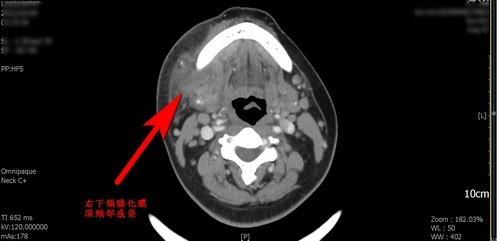

右圖:深頸部感染電腦斷層影像。

年近五旬的鄭女士因發燒、頸部腫痛,到花蓮慈濟醫院急診就醫,會診後耳鼻喉科醫師確診為右下頷腺化膿的深頸部感染,切開引流手術後才消腫,耳鼻喉科主治醫師林廉捷指出,病人是在蛀牙拔除後出現症狀,他提醒民眾如果牙痛治療後,臉部、頸部開始發燒腫痛,就要儘早就醫治療,可避免後續嚴重併發症。

鄭女士到院時發炎指數C反應蛋白達22,遠超過1以下的正常值,入院時張口剩二指幅寬度,僅能喝流質食物,第一線治療先施予抗生素,同時因呼吸道有水腫現象,給予類固醇消腫,但水腫持續擴大影響呼吸,遂執行切開引流手術,林廉捷醫師指出,經檢驗病人是因感染星座鏈球菌化膿往表皮延伸,術後氣管逐漸通暢,一週後化膿排除乾淨就出院,但仍得持續服用抗生素。